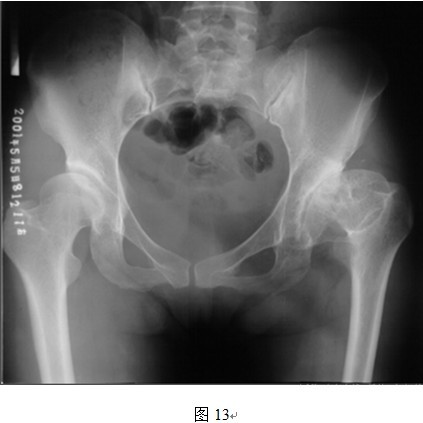

5. THRA不能有效延长肢体

THRA另外一个先天不足就是,从假体本身的设计来看,THRA假体本身不存在延长肢体长度的功能。普通THR的股骨侧假体可通过使用加长头、组配式股骨颈等设计来延长肢体长度,而THRA置换股骨头后,股骨头颈的长度没有明显变化。因此,只能从改变髋臼位置来使得股骨头中心下移,达到部分恢复肢体长度的目的。但是,对于DDH来讲,存在多个不利于肢体长度恢复的因素。首先,DDH假臼形成或者原始髋臼非常浅,加之表面置换不切除头颈情况下阻碍术者视野,想要定位真正的髋臼旋转中心有时比较困难,髋臼下移不一定能够完全实现;其次,即使找到并定位了真臼的旋转中心,但因软组织挛缩严重,术中股骨侧无法充分下移,可能出现无法复位的问题(图6);另外,还有一些患者患侧股骨颈本身就发育短缩或者存在髋内翻(颈干角变小),即使恢复了真臼的旋转中心,股骨侧也可以顺利复位,但是患侧肢体仍旧较对侧短缩(如图13所示左侧股骨颈短缩且内翻,采用THRA无法恢复肢体长度)。

图中所示左侧股骨颈短缩明显,进行THRA后因股骨颈长度不能延长,因此肢体长度不能得到恢复。